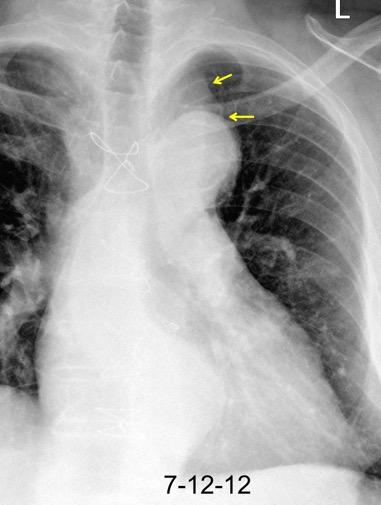

102. HEMATOMA MEDIASTÍNICO.

Hematoma intramural

Disección aórtica

Rotura de aneurisma aórtico

Mediastinitis aguda

Absceso mediastínico

TRAUMA

Rotura esternal

Hematoma mediastínico

Rotura aórtica

Fractura vertebral

Rotura esofágica Perforación esofágica

Mod. de Brandt 2007